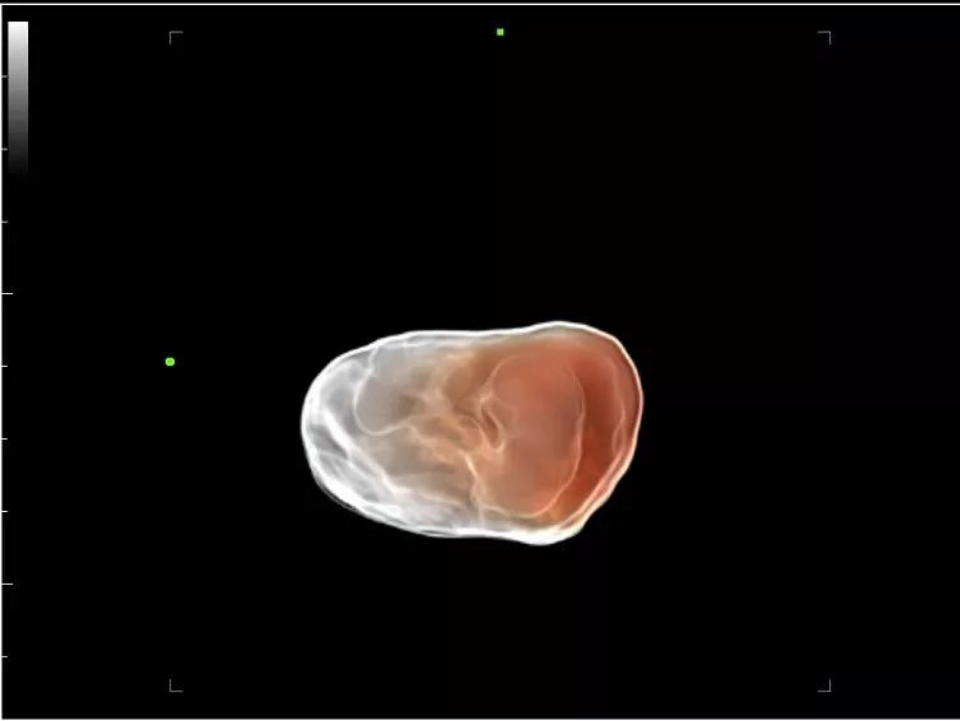

Apart from the speedy hardware structure and premier transducers, X-Insight also significantly optimizes its software to improve scanning efficiency by upgrading iLive to Hyaline — a new rendering method that dynamically applies transparency to rendered structures for a more comprehensive view of anatomy, therefore better displaying internal anatomy from a solid surface. It remarkably improves the detail resolution as well as the anatomical realism of the images.

7W embryo 3D with Hyaline